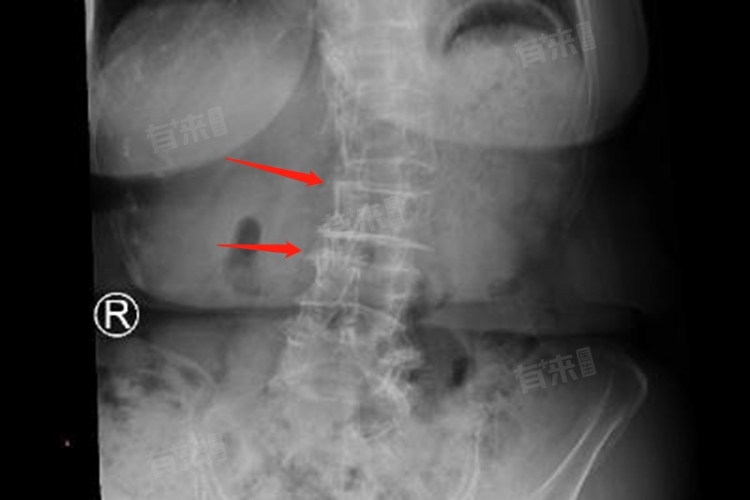

- X线检查:这是最基本的检查方式,能够清晰地显示胸椎的整体形态,包括椎体的形态、椎间隙的宽窄等情况。通过X线片,可以发现椎体边缘是否出现骨质增生,这是胸椎退行性改变的常见表现之一,不过X线检查对于软组织的分辨能力相对较弱。